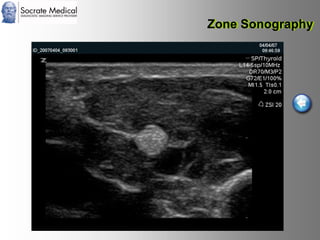

Il documento presenta la tecnologia della zone sonography, che promette una rivoluzione nel campo degli ultrasuoni, superando i limiti dei sistemi tradizionali grazie a metodi di acquisizione dati più veloci e una gestione delle informazioni migliorata. Questa tecnologia consente una maggiore definizione dell'immagine, una riduzione degli artefatti e un'ottimizzazione del processo diagnostico, con vantaggi in termini di tempo e costi. Inoltre, il channel domain processing e la zone speed technology offrono applicazioni avanzate e miglioramenti nella sicurezza diagnostica.